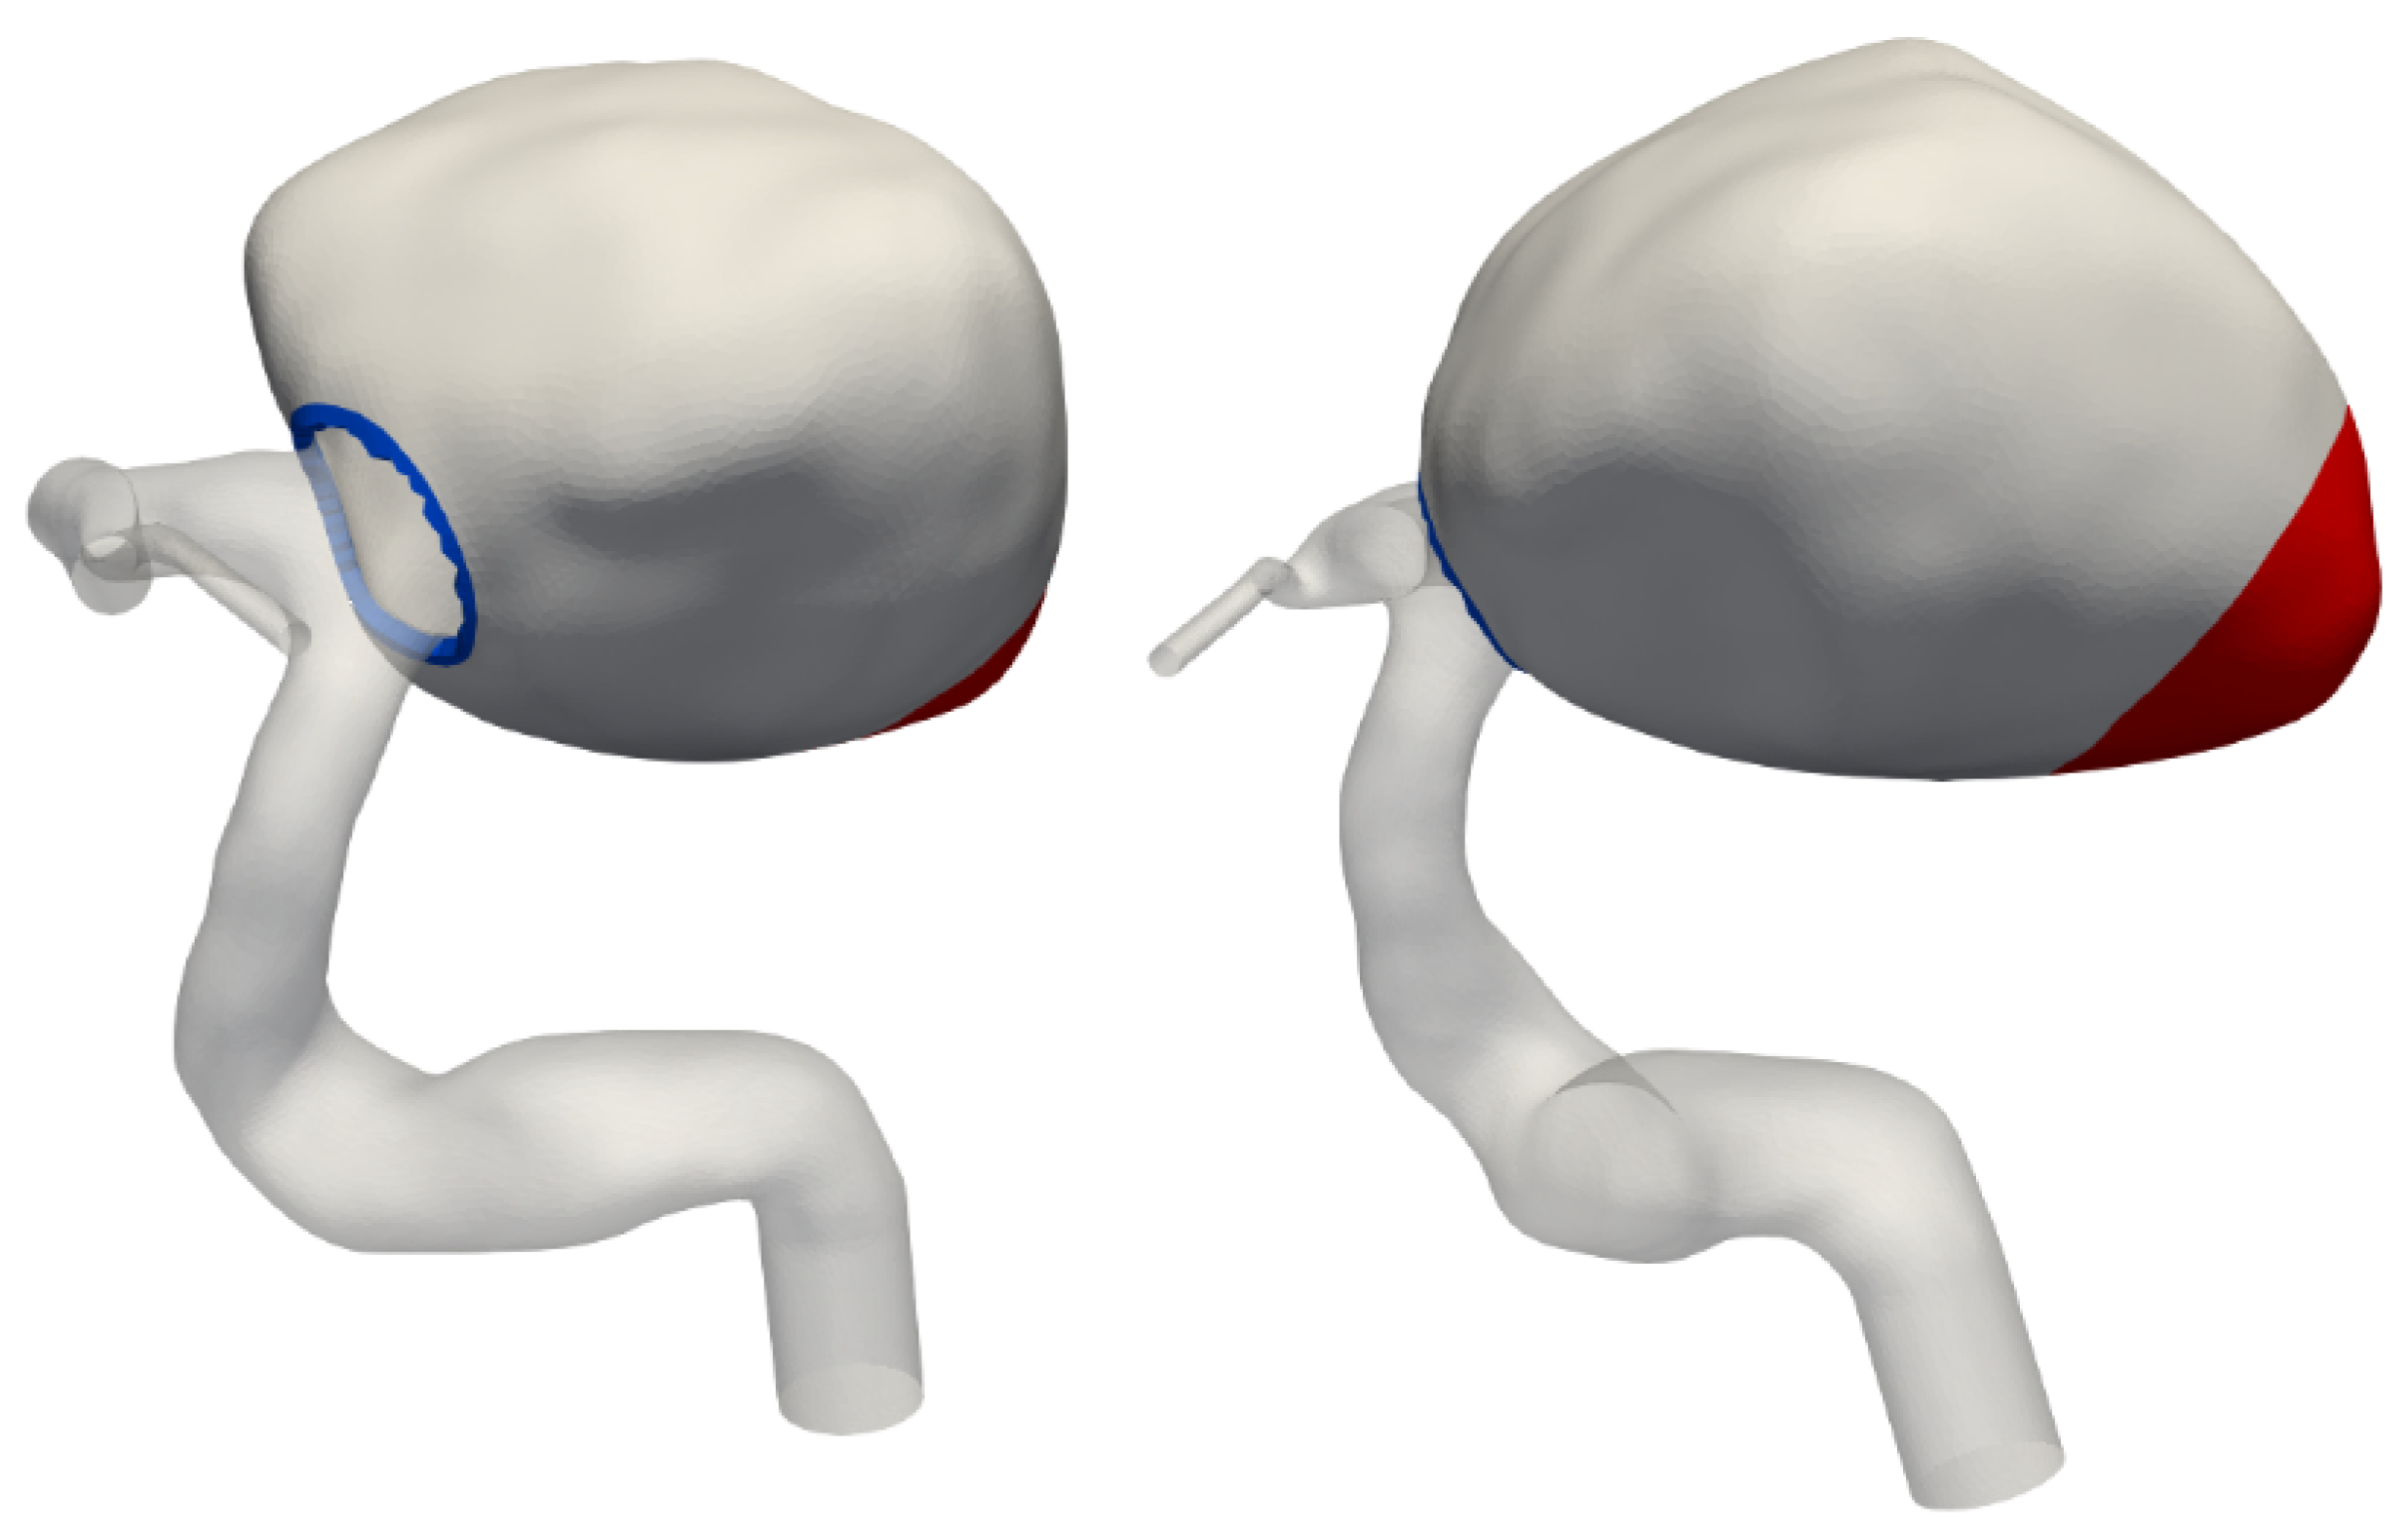

The solid modelling was limited to the aneurysm bulge, as no significant movement was observed in the parent artery or its branches. A solid mesh was extruded from the existing fluid mesh, comprising four layers of tetrahedral elements to achieve a total wall thickness of 0.5 mm (see Figure 3). The Young’s modulus was set to 1 MPa throughout most of the aneurysm, with a reduced value of 0.1 MPa at the tip, as shown in Figure 4. This adjustment reflects the significant movement observed in medical imaging at the tip, a region facing the lateral ventricle. Unlike other sections constrained by surrounding brain tissue, this area experiences less restriction, allowing for greater deformation. These chosen properties have been adjusted to visually match the available rotational angiography data.

Figure 4. Definition of the weaker aneurysm wall region. The weak spot, highlighted in red, faces the lateral ventricle. The blue rim at the neck is clamped in simulations.